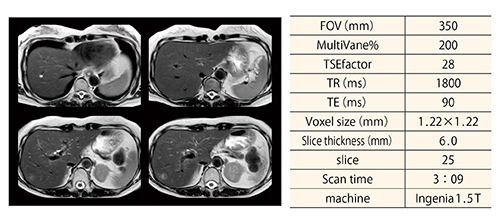

(1) については,従来,腹部領域のダイナミック撮像においてeTHRIVEを利用してきたが,mDIXON XD FFEを利用することで局所磁場不均一に強い正確な脂肪抑制を可能とし,組織造影コントラスト向上を可能とした(図4)。また,従来法では空間飽和パルスの併用ができず,造影後に血管の高信号によるゴーストアーチファクトが発生していた。mDIXON XD FFEではk-spaceのセグメンテーションが可能となり,空間飽和パルスを併用することで血管によるゴーストアーチファクト低減を可能とした。

図4 mDIXON XDを利用したT1WI FFE画像

k-spaceのセグメンテーションを行うことで,空間飽和パルスを利用可能となり,大動脈からの血流アーチファクトを抑制可能である。(a)ダイナミックプレ画像(b)肝早期相(c)門脈相(d)平衡相である。

(画像ご提供:熊本中央病院様)